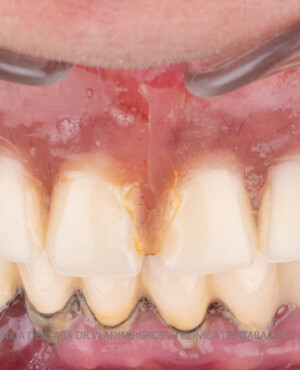

Caz 1